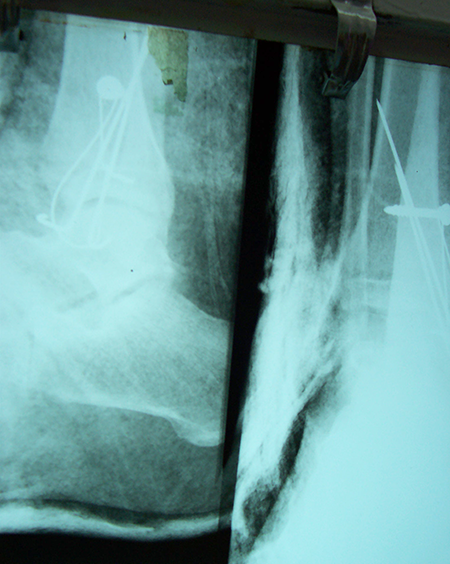

A male patient, aged 58 years had been diagnosed to have Closed comminuted fracture calcaneum . Closed reduction and percutaneous fixation done with CC Screw.

Pre-Operative

Post-Operative